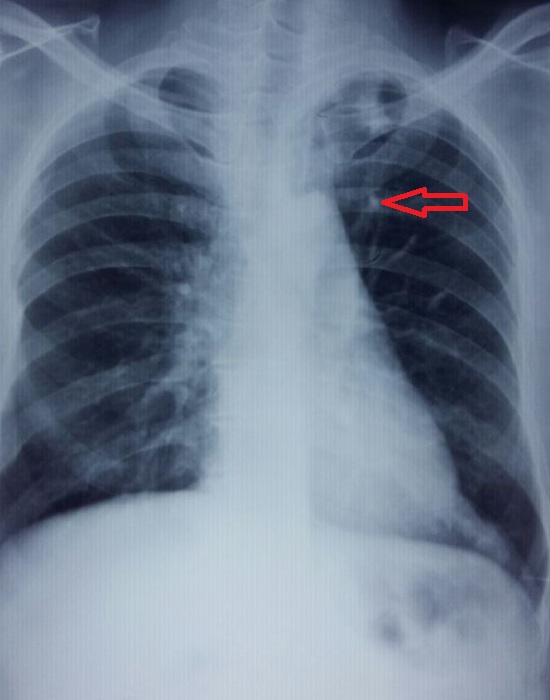

A case of Pulmonary Hamartoma

Pulmonary hamartoma, hemoptysis, fibromyxoid stromaAbstract